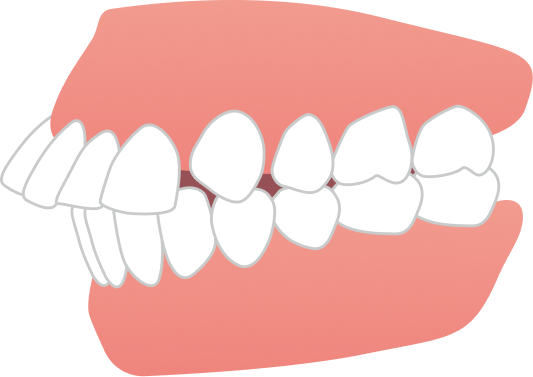

30代男性 出っ歯とガタガタが気になる

30代男性の患者さまで、上の前歯の前突感とガタつきを主訴にご相談に来院されました。目立たず、日常生活への負担をできるだけ抑えながら治療を進めたいというご希望を踏まえ、当院で専門的に行っているマウスピース矯正にて治療を開始しました。

治療では、歯列全体のバランスと噛み合わせを考慮しながら計画を立て、抜歯を行うことなく、マウスピースのみで治療を進めました。治療期間は1年9ヶ月で、見た目の印象が大きく改善するとともに、機能的にも安定した噛み合わせが得られています。

自然な口元と噛みやすさの両立を実現できた症例です。

BEFORE